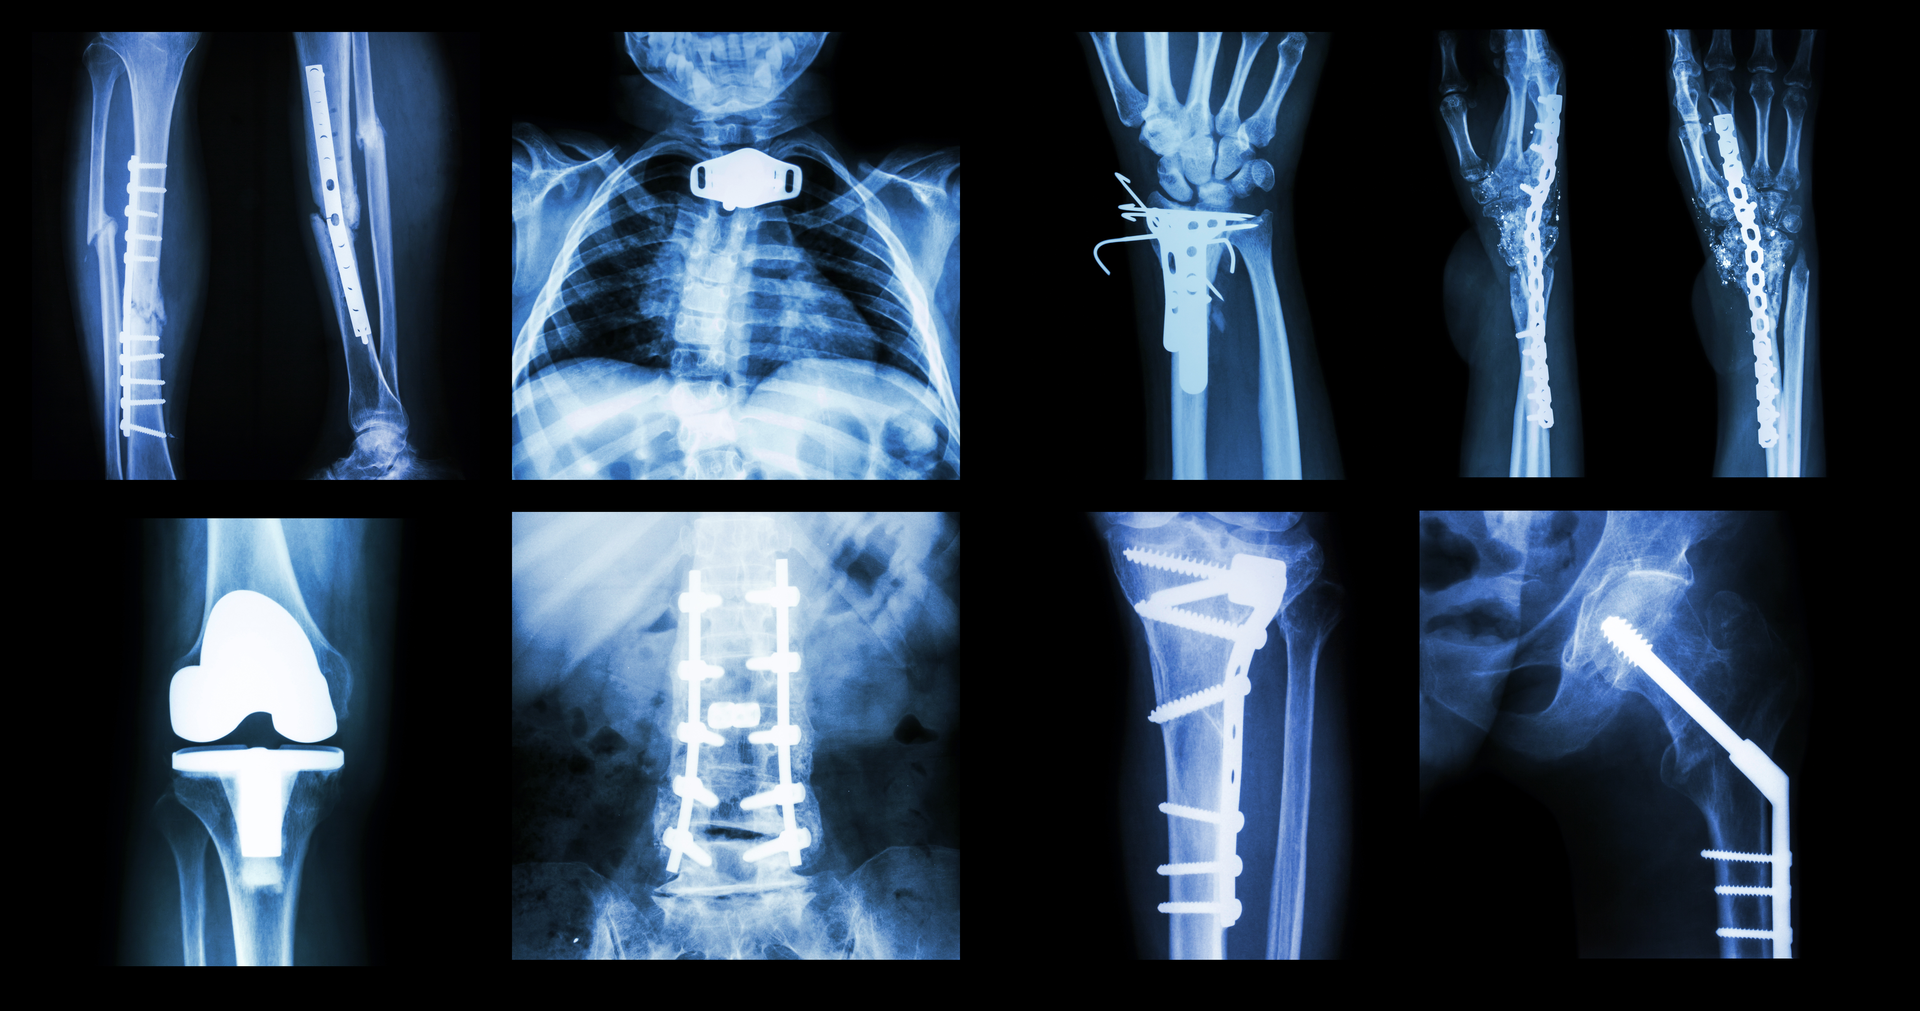

“Orthopedic surgeons are experts at the repair of various fractures and defects that cause impairment and pain to everyday life in individuals throughout the world,” Bulman said. “Their days are long, but they are problem solvers by nature and want those problems solved yesterday. To that end some will take matters into their own hands and proactively work to find vendors that can help solve these issues. At Brasseler Surgical, we help deliver value and quality by aligning with IDNs so that conversations about pricing, standardization and contract compliance are more intentional than transactional.